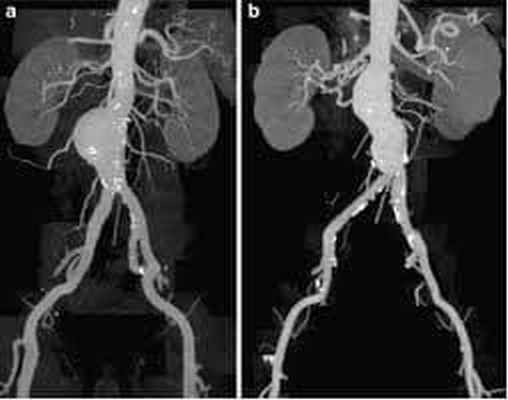

Эндопротезирование аорты

Более современный метод лечения аневризмы брюшной аорты, относящийся к гибридной хирургии. Данный метод сочетает в себе открытые хирургические технологии с эндоваскулярными, он представляет собой замену аневризматически расширенного участка аорты изнутри с использованием специального протеза, изготовленного в большинстве случаев «под заказ» (этим объясняется его высокая стоимость). Сосудистый протез специальным образом уложен в системе доставки. Его расправляют прямо в полости аневризмы, под контролем рентген-установки. Таким образом, протез исключает воздействие системного артериального кровотока на слабые растянутые стенки аорты.

Этот метод позволяет добиться результатов, сравнимых с открытой хирургической техникой, только с меньшим количеством осложнений, уменьшением сроков госпитализации и реабилитации пациента в 2 раза! Ограничивают применение этого современного метода только некоторые анатомические параметры самой аорты и высокая стоимость эндопротеза.